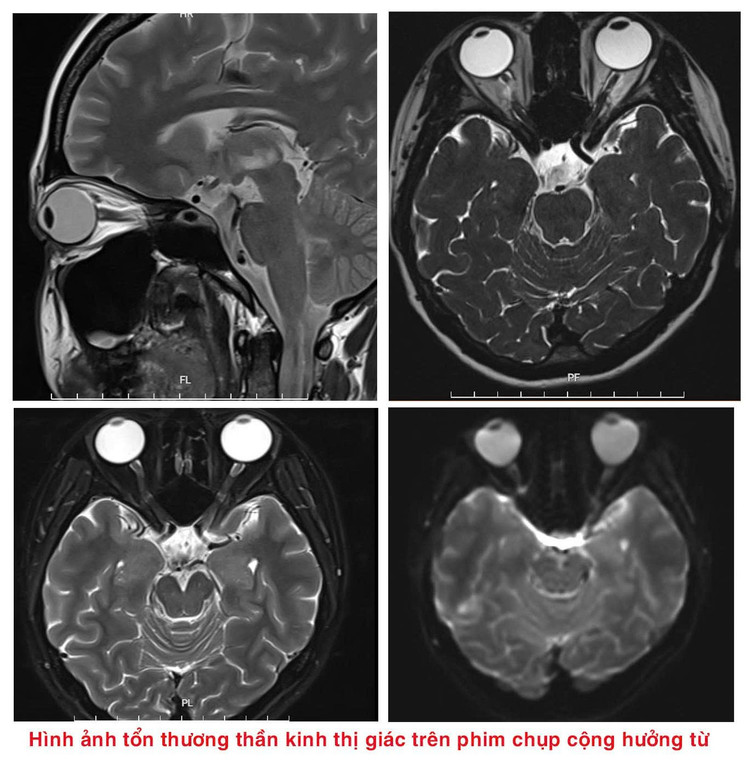

Tại đây, người bệnh được các bác sĩ thăm khám, làm xét nghiệm máu, chọc dịch não tuỷ, chụp cộng hưởng từ sọ não,… Sau hội chẩn lâm sàng, người bệnh được kết luận bị rối loạn Phổ viêm tuỷ thị thần kinh thể tổn thương thần kinh thị, sàn não thất IV, hành tuỷ lưng bên.

Trong đó, Viêm thị thần kinh là viêm dây thần kinh thị giác, gây đau nhức trong mắt, đau tăng khi cử động mắt và thường tiến triển nhanh tới giảm thị lực hoặc mù lòa. Triệu chứng thông thường khởi phát từ 1 mắt, tuy nhiên cũng có thể xảy ra đồng thời cả 2 mắt hoặc tiến triển từ một bên sang 2 bên.